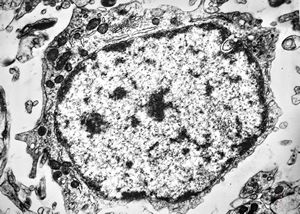

F,50y. | progressive multifocal leukoencephalopathy- viral particles in a glial cell